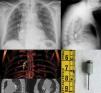

El paciente acude al Servicio de Urgencias desde una consulta odontológica realizada una hora antes en la que, mientras se le practicaba una endodoncia, una broca cae accidentalmente en la cavidad bucal y desaparece, el dentista cree que ha sido deglutida y lo remite a nuestro hospital. El paciente acude asintomático y en la radiografía de tórax y en la TAC (fig. 1) se observa la broca en el bronquio intermediario, sin complicaciones asociadas. Bajo sedación, se realiza fibrobroncoscopia por vía oral y con fórceps de cocodrilo se extrajo todo en bloque (fig. 1), procediéndose al alta en 24h.